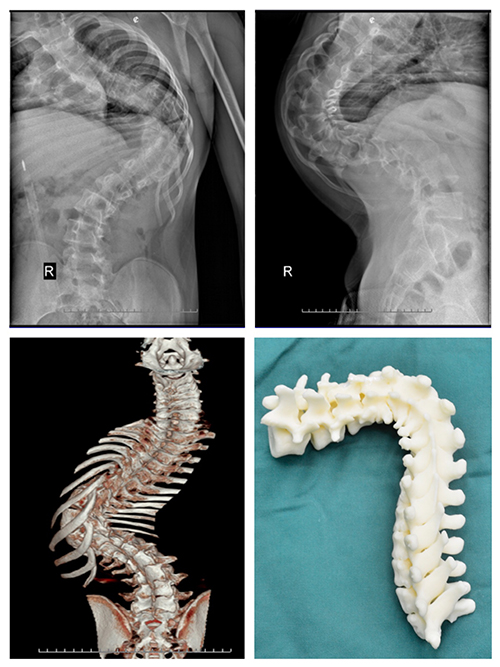

案例二:患者李某,男,16岁,文山州广南县某中学学生。2007年(6岁时)发育时发现双侧肩背部不等高,当地县医院诊断为“脊柱侧弯”。同样也是由于治疗技术所限,10年来,他脊柱侧弯逐渐加重,跑动时出现运动耐量下降。相比陶某,他平时行走尚未出现喘息。李某于8月初到少妇色情 就诊,收入骨科。

骨科医生经过对李某进行脊柱X线片,三维CT及MRI等项检查,发现侧弯Cob角达135°,后凸Cob角达80°,并发现患者胸椎有半椎体畸形。